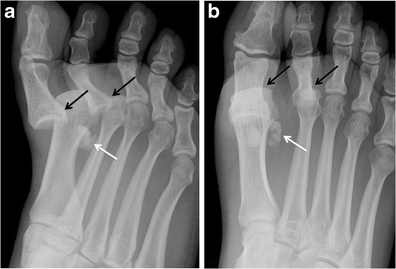

Sesamoid Bone X Ray Collection 2022 Sesamoid Bone X Ray Collection 2022

Sesamoid Bone X Ray

Sesamoid fracture | Radiology Reference Article | Radiopaedia.org Radiology Review - Sesamoid fracture | Axis Sports Med Toes (sesamoid view) | Radiology Reference Article | Radiopaedia.org Sesamoid | Radiology Reference Article | Radiopaedia.org Sesamoid bone - Wikipedia Sesamoid Bone X Ray